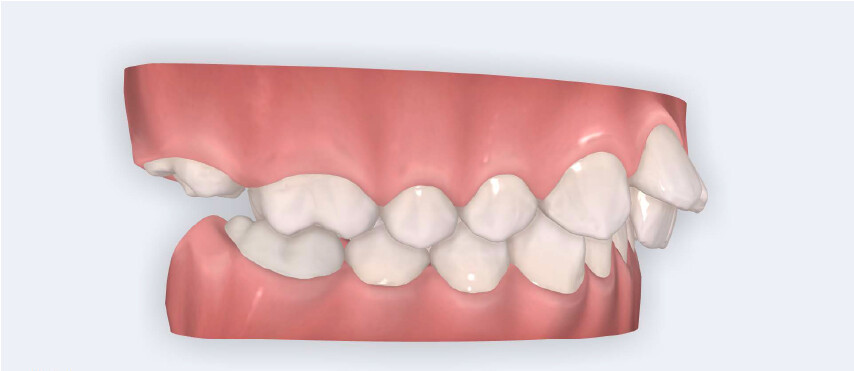

A 13-year-old male patient presented with a deep bite, characterized by near-complete coverage of the mandibular incisors. Clinical evaluation revealed bi-arch crowding, dental rotations, and proclination of the maxillary lateral incisors, contributing to the patient’s esthetic concerns. The facial profile was retrusive, consistent with mandibular retrognathism, and no significant periodontal abnormalities were detected.

The patient presented with a skeletal Class II relationship with bilateral molar and canine Class II and a Class II division 2 dental pattern. The deep bite was associated with anteroinferior crowding and an accentuated Curve of Spee. Facial analysis revealed good symmetry, a slightly increased lower facial third, and a convex profile characterized by mandibular and chin retrusion. Lip competence was mildly reduced, with a decreased nasolabial angle and mentalis hyperactivity, all of which compromised overall facial harmony.